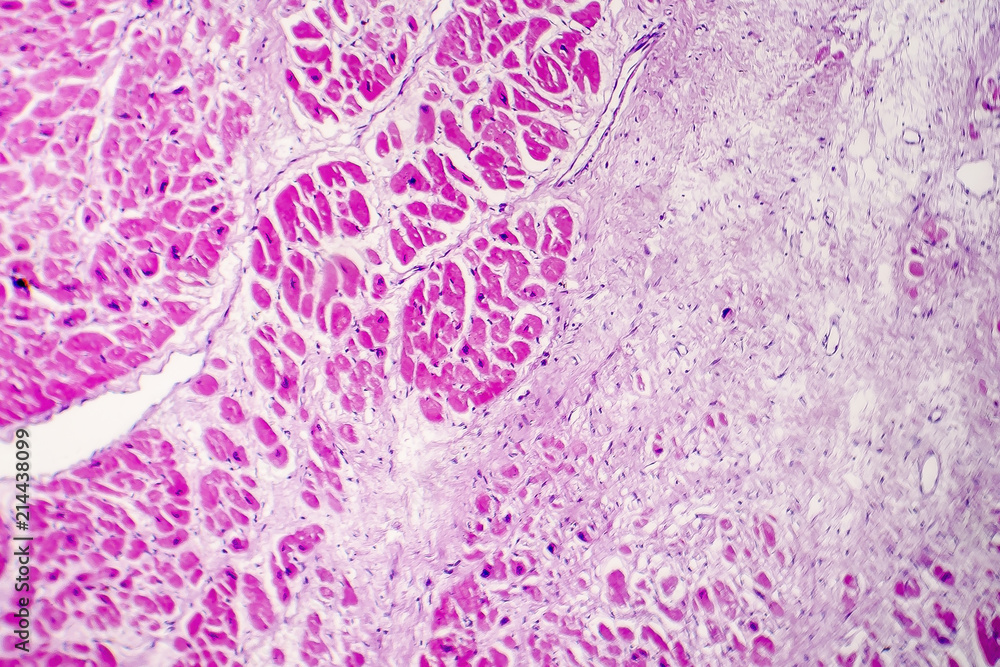

Межуточный миокардит: гистологические исследования